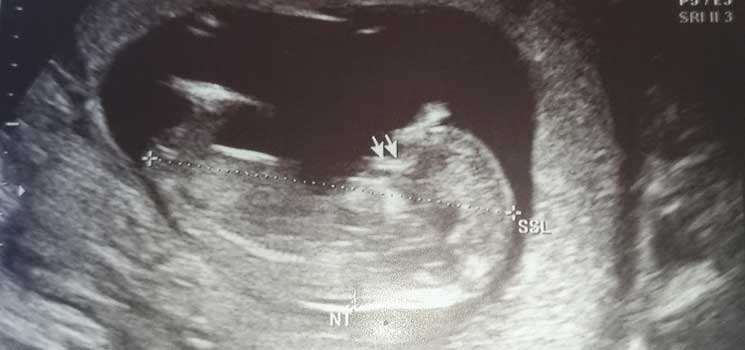

Erleichtert ins zweite Trimester - Tagebücher aus der Schwangerschaft von Lina aus Traunstein